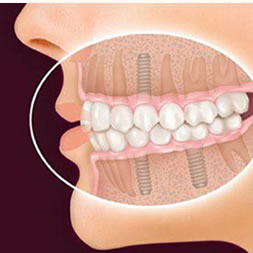

Best Dental Implants in Ahmedabad

32 Pearls : Multi Speciality Dental Clinic & Implant Centre is Ahmedabad based leading dental clinic founded by Dr. Jaimin Patel(MDS, FRHS, FICOI-USA), With highly skill full team of dentist and high-tech technology, Dr. Jaimin Patel serving most trusted treatment of all type of oral health include, Dental Implants, Tooth Filling Covered, Child Dental Care, Full Mouth Rehabilitation, Fixed (ceramic) Teeth, Laser Dentistry, Painless R.C.T., Smile Makeover etc. 32 Pearls Dental serving since last twelve years with 100% guaranteed treatment of dental treatment.